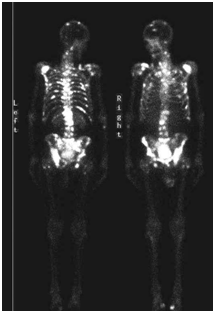

back or bone pain due to spread to the bones.

Stage 4: Spread to distant organs like lymph glands, bone, liver,lungs.(Not curable but still better

survival than other cancers of similar stage)

MRI SCAN/PET SCANS will help diagnose the stage of disease.